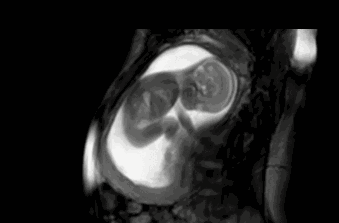

胎儿是很聪明的,一般从怀孕四个月起,胎儿就有了敏感的听觉,所以孕中期可以开始做胎教,刺激胎儿的听觉神经发育。

胎儿的听觉系统在孕期就已经发育,胎儿在孕六个月的时候,能听到外界的声音,包括妈妈的说话声,呼吸声。所以,孕期做胎教还是很有必要的,而且胎儿能感觉到,但并不一定能完全理解胎教中的全部意思。

我是二胎妈妈,孕期6个月的时候就明显感觉到胎宝宝对声音很敏感。每次播放胎教音乐的时候,胎儿就会随着音乐动起来,可以感觉到宝宝很兴奋。原来,4个月的时候胎儿听觉器官已初步发育完全,但对接收外界声音还是比较模糊,但到了第6 个月时,胎宝宝的听力就与成人无异了,真的是神奇。